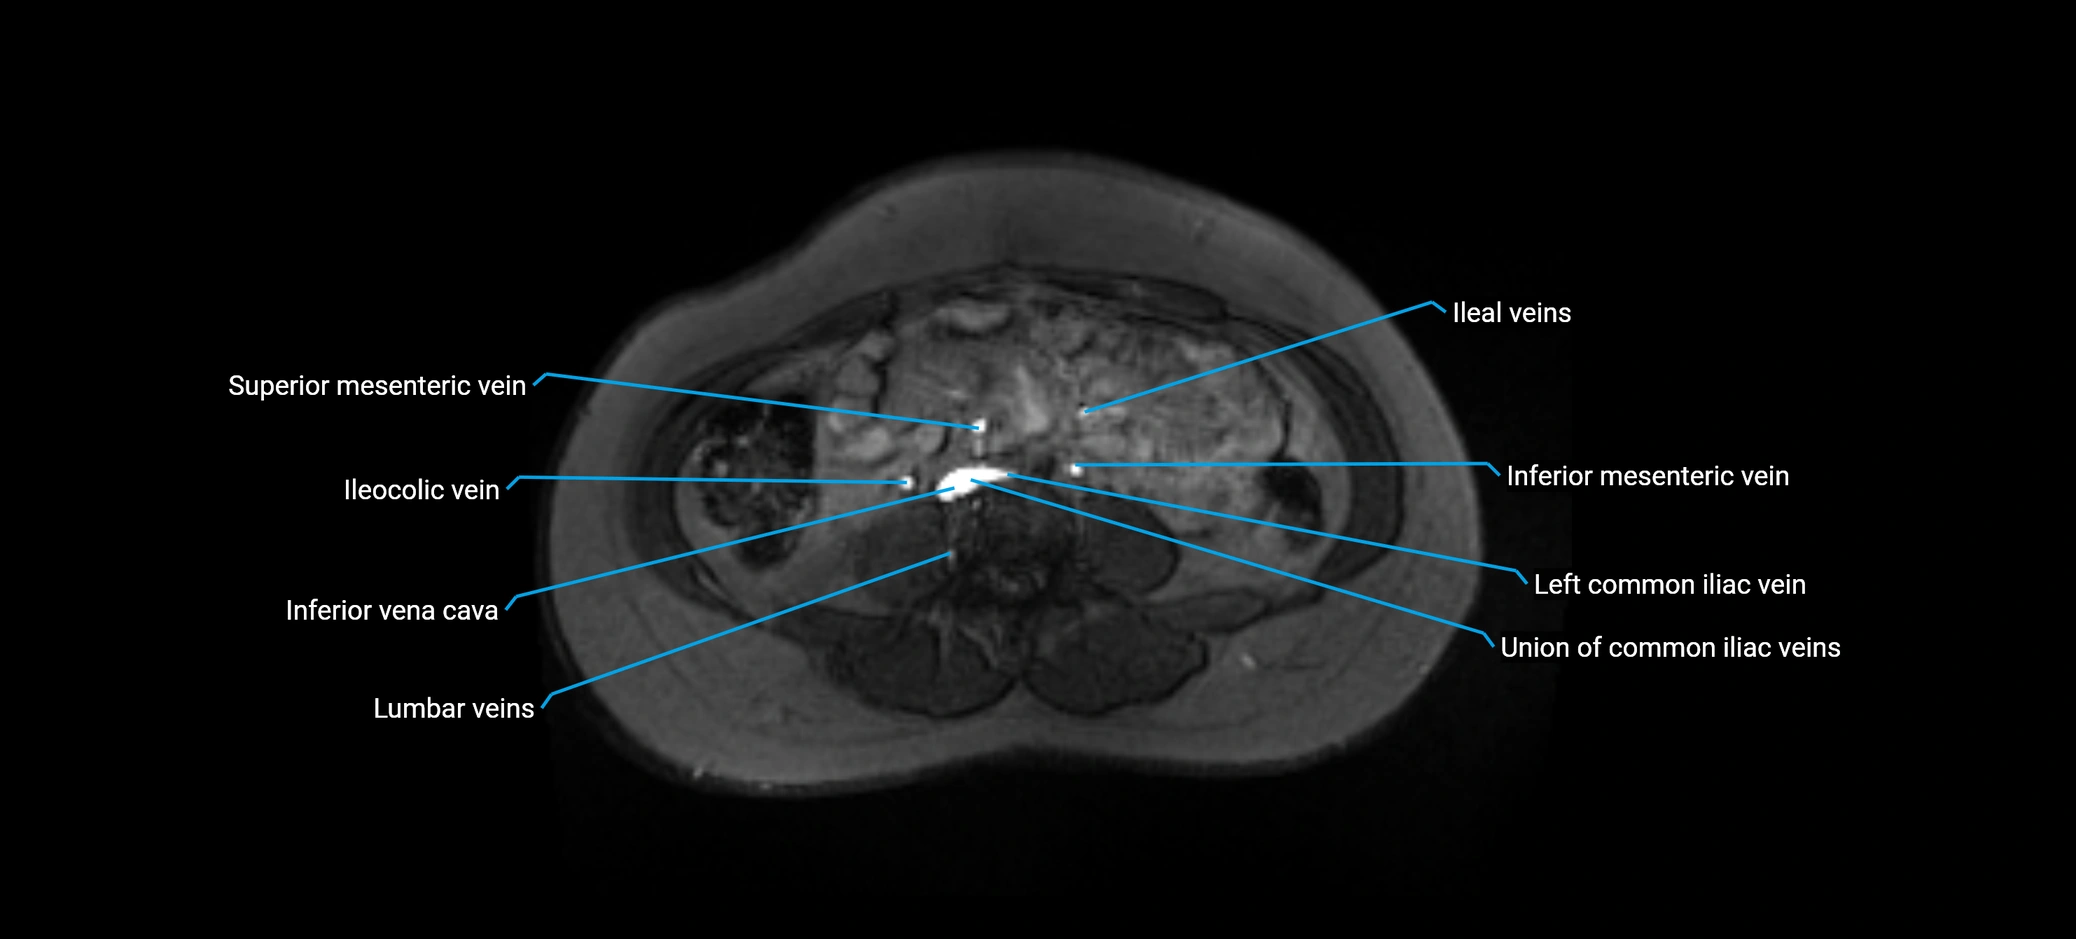

MRI image

image